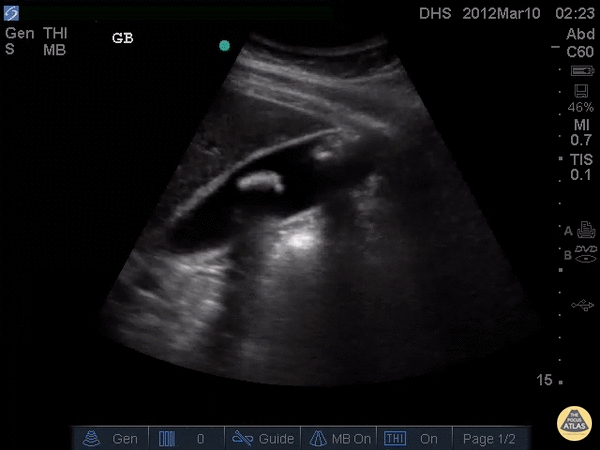

One Minute Image Review

One-Minute Image Review: High yield bite sized learning! Voice annotation of both normal and abnormal point of care ultrasound clips!